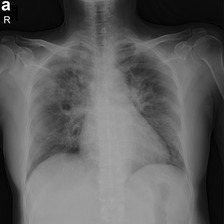

Across the world's coronavirus disease 2019 (COVID-19) hot spots, the need to streamline patient diagnosis and management has become more pressing than ever. As one of the main imaging tools, chest X-rays (CXRs) are common, fast, non-invasive, relatively cheap, and potentially bedside to monitor the progression of the disease. This paper describes the first public COVID-19 image data collection as well as a preliminary exploration of possible use cases for the data. This dataset currently contains hundreds of frontal view X-rays and is the largest public resource for COVID-19 image and prognostic data, making it a necessary resource to develop and evaluate tools to aid in the treatment of COVID-19. It was manually aggregated from publication figures as well as various web based repositories into a machine learning (ML) friendly format with accompanying dataloader code. We collected frontal and lateral view imagery and metadata such as the time since first symptoms, intensive care unit (ICU) status, survival status, intubation status, or hospital location. We present multiple possible use cases for the data such as predicting the need for the ICU, predicting patient survival, and understanding a patient's trajectory during treatment. Data can be accessed here: https://github.com/ieee8023/covid-chestxray-dataset